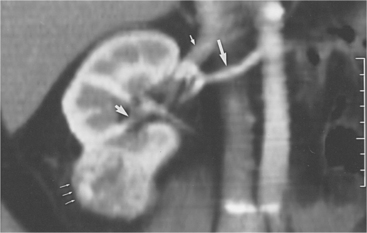

The primary feature of RCC is the renal parenchymal mass, which can be detected by a variety of imaging modalities (Fig. 18-2). The widespread availability of abdominal ultrasound (Fig. 18-3), magnetic resonance imaging (MRI), and CT scanning has increased the diagnosis of incidental renal tumors.

Figure 18-2 Renal cell carcinoma on computed tomographic scan. A reconstructed image in the coronal plane of section shows vascular anatomy by demonstration of the renal artery (large arrow), renal vein (small arrow), excretion into the pelvicaliceal system, which is not obstructed (arrowhead); and renal cell carcinoma arising from the lower pole of the right kidney (thin arrows). The cancer is confined to the cortex; therefore, partial nephrectomy can be performed. (From Brenner BM: Brenner and Rector’s The kidney, ed 7, Philadelphia, 2004, Saunders.)